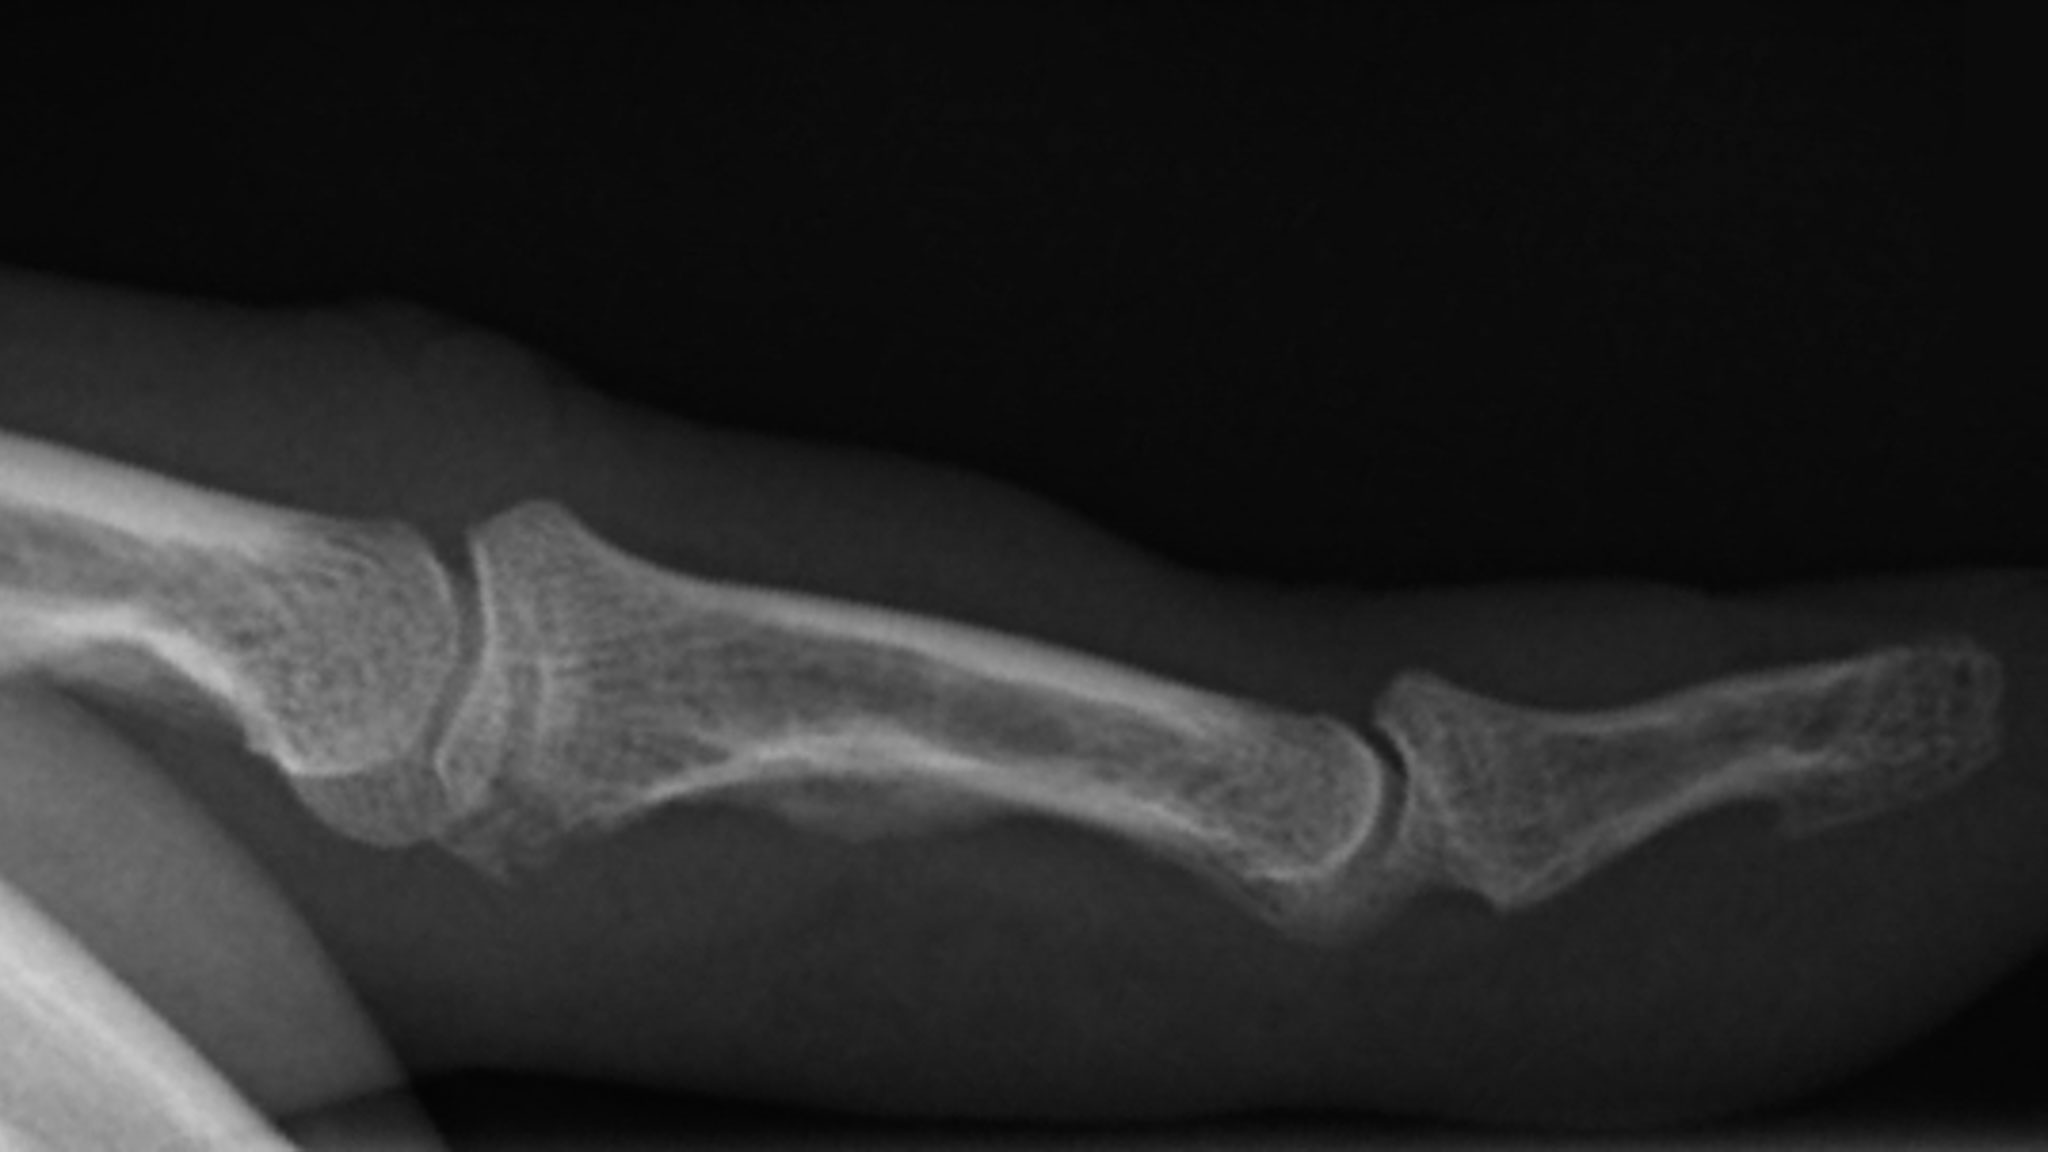

Das Selfie vor den Kreidefelsen hat übrigens unseren vollen Einsatz mit heftigen Schmerzen gefordert. Bei einem Versuch hat es mir nämlich auf dem Weg von der Kamera zur wartenden Maria auf einem rutschigen Felsblock die Füße weggezogen, so dass ich sehr unsanft auf dem Bauch landete. Die linke Hand ist nun heftig geprellt und geschwollen, so dass ich diese im Moment gar nicht mehr richtig nutzen kann. An der rechten Hand schmerzt der Daumenmuskel so sehr, dass auch an dessen Einsatz gerade nicht wirklich zu denken ist. (Das Packen unserer Sachen heute Abend muss wohl Maria zu einem Teil übernehmen und meine Schuhe muss ich morgen früh wohl auch von ihr binden lassen.)

Nachdem eine Woche später die Heilung noch nicht so gut vorangeschritten war, wie ich das erhofft hatte, bin ich am 25. Dezember ins Klinikum gegangen. Von 11 bis 18:30 Uhr war ich dort, habe in dieser Zeit dreimal für wenige Minuten mit einem Arzt gesprochen und bin einzelne Minuten lang geröntgt worden – den Rest der Zeit habe ich gewartet! Spezialisten unter euch (und nur solche) werden erkennen, dass da am mittleren Glied meines linken Ringfingers eine kleine Knochenabsplitterung zu sehen ist. ☹️